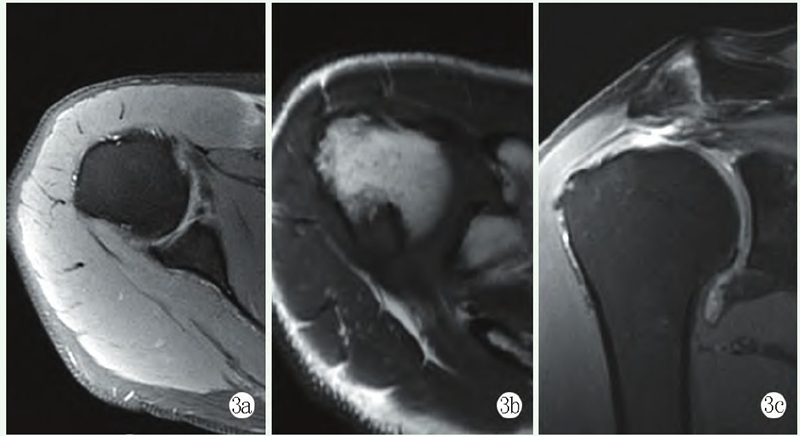

影像学检查:X线片显示肩峰外缘增生,肱骨头上移,肩峰-肱骨距离短缩(图2a)。MRI示:右冈上肌全层撕裂并回缩,轻度脂肪浸润,肱二头肌长头腱断裂(图2b),诊断为右肩袖损伤。

图2a: 术前 X 线片示肩峰外缘增生,肱骨头上移,肩峰-肱骨距离短缩;2b: 术前 MRI 显示右冈上肌全层撕裂并回缩,轻度脂肪浸润,肱二头肌长头腱断裂